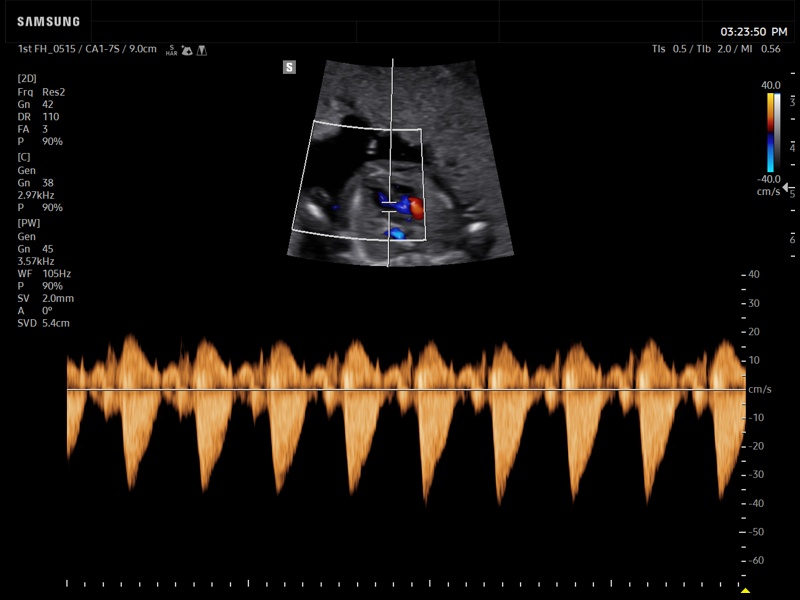

Fetal heart (LVOT), CFM & PW

Fetal heart (LVOT), CFM & PW (echogramm №938)

[RU] Ultrasound image №938: Fetal heart (лeft ventricular outflow tract) in CFM (color flow mapping) and PW (pulsed wave) mode. 1-st trimester, convex probe 1-7 MHz.

Echogramm was received by ultrasound scanner Z20 (new model).